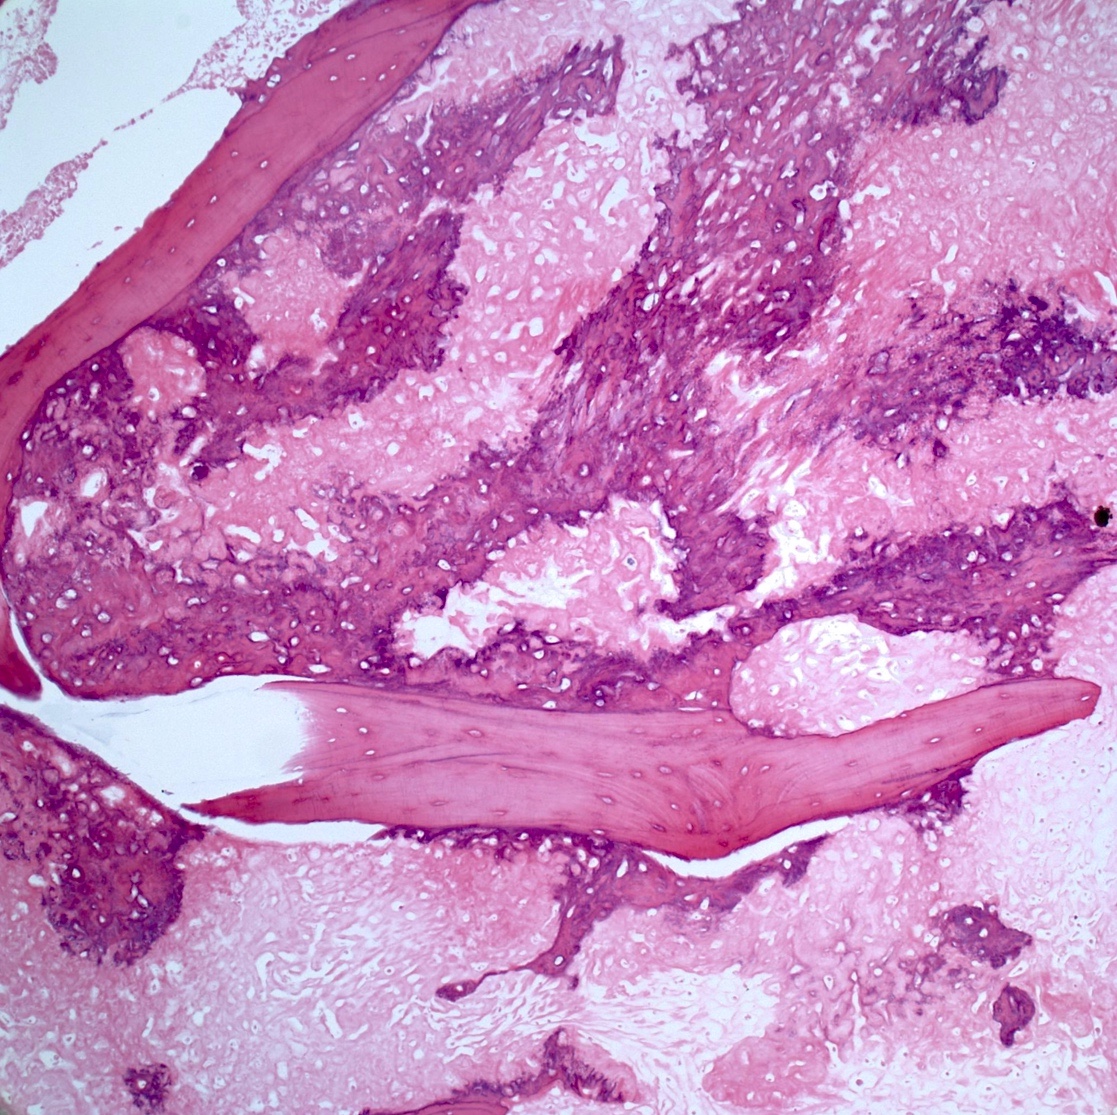

- Periosteal osteosarcoma:

- Ossified mass: intimately attached to native cortex (secondary to endochondral ossification)

- Pericortical bone: dense, mature bone

- Bony spicules: radiate from the dense pericortical bone peripherally and admix with the hyaline cartilage component

- Large vascular cores in center of bony spicules

- Periphery of spicules is calcified / osseous or chondro-osseous and merges with (atypical) hyaline cartilage

- Periphery of mass (majority of the tumor’s volume):

- Atypical hyaline cartilage (appearance of grade 1 - 3 chondrosarcoma); may have myxoid change

- Osseous component (always present but not the dominant component): intermediate grade osteosarcoma intermixed with cartilaginous component; may have lace-like bone but large areas of conventional osteoblastic osteosarcoma are not present

- May have an admixed fibroblastic component (fascicles of mitotically active spindle cells)

- Ossified mass: intimately attached to native cortex (secondary to endochondral ossification)

Microscopic (histologic) images

Contributed by Jesse Hart, D.O., Borislav A. Alexiev, M.D. and AFIP

Practice question #2

A 16 year old boy had a biopsy from a 16 cm mass in the proximal humerus (see image). Which of the following is true?

Practice answer #2

C. Treatment will include neoadjuvant chemotherapy followed by resection. This is a conventional high grade osteosarcoma.